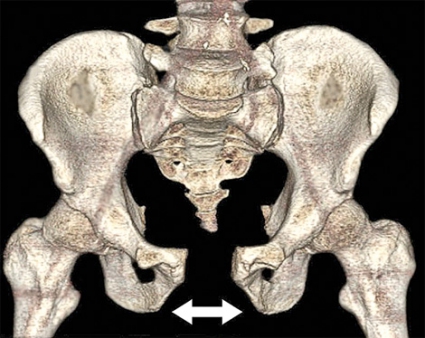

• Vertikalt våld, vilket ger vertikal fraktur i sakrum, i sakroiliakaled eller ilium och med vertikal dislokation. Skadan uppkommer vanligen vid fall från höjd (Figur 4, underst).